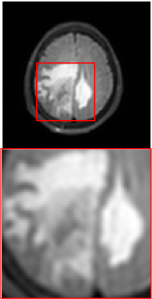

Figure 5 provides the qualitative comparison of the various methods on the four datasets at a scale of 4. The top, second, third, and bottom rows are the SR results under the FastMRI, clinical brain, clinical tumor and clinical pelvic datasets, respectively. The red boxes indicate the zoom-in region of complicated anatomical structures along with their corresponding error maps. Note that the brighter textures in the error maps, the lower the quality of the reconstructed images. As can be seen, compared to methods based on Transformers and CNNs, diffusion-based methods like DisC-Diff and DiffMSR (Ours) are capable of reconstructing high-realistic images with promising reconstruction metric scores (PSNR and SSIM). Nevertheless, while DisC-Diff can reconstruct high-precision MR images, it does not preserve the structure present in the original HR images, introducing some additional information that can affect medical diagnosis. In contrast, our method combines DM and PLWformer, which can preserve the original image’s structure while restoring high-frequency information.

In this section, we present more visual qualitative comparisons. Figures 8, 9, 10, and 11 show the reconstruction results of each method in FastMRI, clinical brain, clinical tumor, and clinical pelvic, respectively. As can be seen, although DisC-Diff can reconstruct MR images with high-frequency information, it fails to preserve the structure and content of the original Target HR image effectively, resulting in image distortion. In contrast, our proposed DiffMSR can restore high-frequency information while preserving the structure of the original HR image, indicating the effectiveness of the joint use of DM and PLWformer.